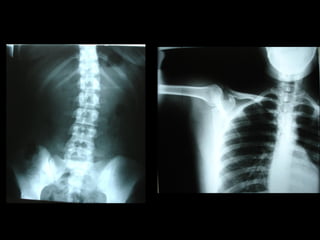

Radiografía

Lateral

De Cara